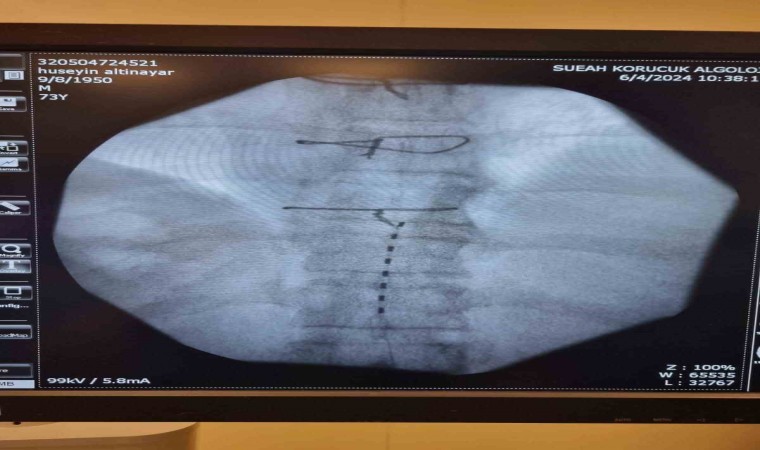

Yıllardır ayağındaki ağrıya çare bulamayan hasta Sakarya Eğitim ve Araştırma Hastanesi (SEAH) Algoloji Kliniğine başvurdu. 7 yıldır ayağında yanma ve ağrı şikayeti (Kronik nöropatik hastalığı) olduğunu belirten hastanın şikayetlerinin son bulması için klinik hekimleri tarafından özellikli bir işlem olan Ağrı Pili (Spinal Kord Stimülatörü) uygulanmasına karar verildi. Algoloji Kliniğinde Prof. Dr. Kemal Nas, Doç. Dr. Savaş Şencan, Uzm. Dr. Rıdvan Işık ve Asistan Dr. Sena Ünver tarafından işleme alınan hastanın operasyonu başarıyla tamamlandı.

İşlem sonrası servise alınan hastanın uzun yıllardır hayatını olumsuz etkileyen müzmin ayak ağrısının geçtiği belirtilirken, ağrı uzmanı hekimler tarafından uygulanan yöntemin son derece etkili bir tedavi olduğu kaydedildi. Şifayı SEAH’ta bulan hastada hayat konforunu etkileyen ağrıdan kurtulduğu için mutlu olduğunu dile getirdi.